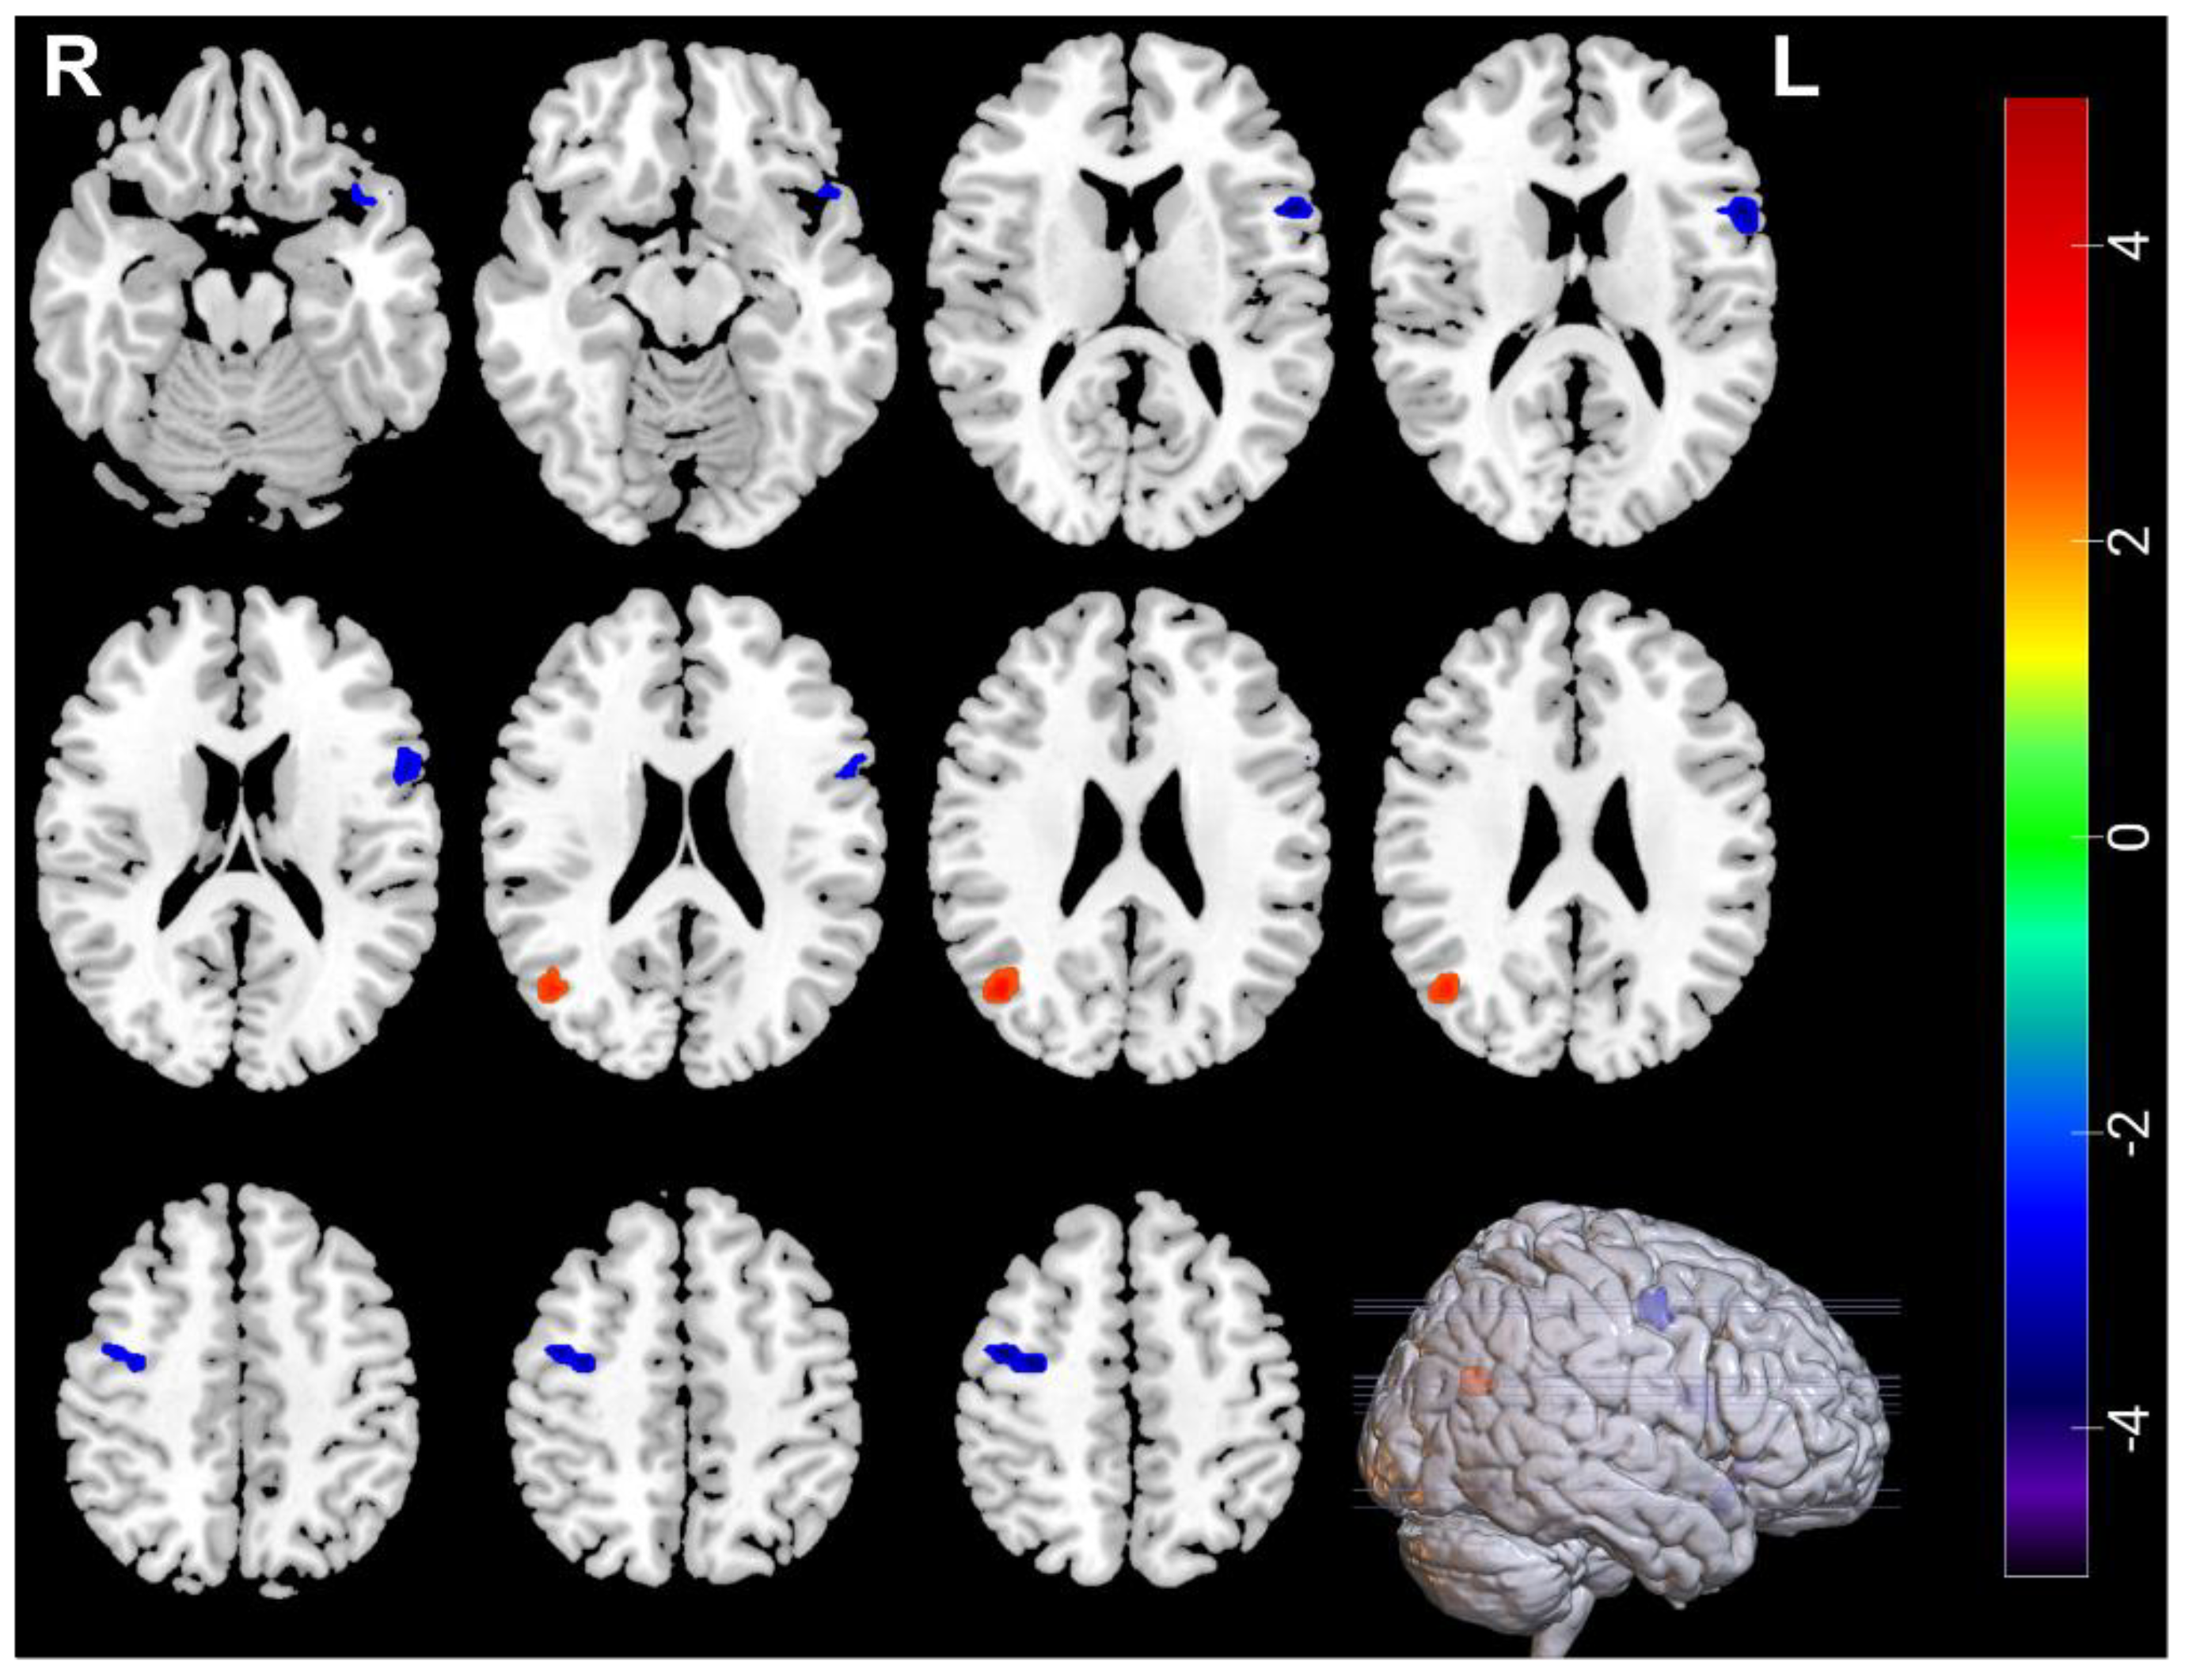

| Measures | Brain Regions | Voxel Size | Peak t Value | MNI Coordinates | ||

|---|---|---|---|---|---|---|

| Decreased | ||||||

| ALFF | Amygdala_R | 31 | −4.637 | 33 | 0 | −21 |

| ALFF | Temporal_Inf_L | 30 | −3.6166 | −51 | −24 | −18 |

| ReHo | Temporal_Inf_L | 45 | −4.3107 | −48 | −21 | −18 |

| Increased | ||||||

| ReHo | Frontal_Inf_Oper_R | 40 | 4.0503 | 63 | 15 | 15 |

| ReHo | Occipital_Mid_L | 41 | 3.7464 | −36 | −84 | 6 |